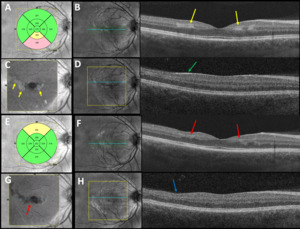

Best-corrected visual acuities were 20/20-1 right eye and 20/20-1 left eye. Pupils were equally round and reactive to light without an afferent pupillary defect. Extraocular movements were smooth and full in both eyes. Confrontation visual fields were full to finger counting in each eye. Amsler grid testing revealed a small area of metamorphopsia temporal to fixation in the right eye and small areas of metamorphopsia nasal and superotemporal to fixation in the left eye. Red cap testing was equal between the eyes. Slit lamp examination of the anterior segment was unremarkable in both eyes. Intraocular pressures by Goldmann applanation tonometry measured 14 mm Hg in each eye. Dilated fundus examination revealed a cup-to-disc ratio of 0.25 in each eye with well-perfused neural retinal rim tissue without edema or pallor. Examination of the posterior pole revealed mild retinal whitening superotemporal to the fovea in both eyes, a cotton wool spot in the inferior nasal arcade and a cotton wool spot in the inferior temporal arcade of the right eye, and 2 cotton wool spots in the superior temporal arcade of the left eye (Figure 1). The arterial-to-venous ratio was 2/3 in both eyes with no vascular tortuosity and no visible emboli. The peripheral retina was flat without holes, tears, or breaks in both eyes. Optical coherence tomography of the retinal nerve fiber layer revealed thick retinal nerve fiber relative to the normative database (not indicative of subclinical edema but rather due to his young age) inferiorly and nasally in both eyes with average retinal nerve fiber layer thickness of 127 microns in the right eye and 123 microns in the left eye (Figure 2). Optical coherence tomography showed central subfoveal thickness of 275 microns in the right eye (Figure 3A) and 271 microns in the left eye (Figure 4A). There were parafoveal hyperreflective bands in the inner nuclear layer worse in the right eye (Figure 3B) compared with the left eye (Figure 4B). En face optical coherence tomography at the level of the mid-retina showed patchy hyperreflectivity worse in the right eye (Figure 3C) compared with the left eye (Figure 4C), which corresponds to the inner nuclear layer hyperreflectivity on cross-section. Interestingly, in this case, there is also hyperreflectivity of the internal limiting membrane superotemporal to the fovea in both eyes (Figures 3D and 4D, right and left eye, respectively) that corresponds to the areas of retinal whitening seen on fundoscopy. The superficial capillary plexus on optical coherence tomography angiography showed an abnormal foveal avascular zone with small patches of capillary dropout worse in the left eye (Figure 5C) compared with the right eye (Figure 5A); the deep capillary plexus showed multifocal ovoid areas of signal attenuation due to capillary dropout in both eyes (Figures 5B and 5D, right and left eye, respectively).

He was monitored at 4-week intervals but was lost to follow-up after the 3-month visit. Visual acuity improved to 20/20 in each eye at the 1-month follow-up and remained stable throughout the clinical course. Despite this, small areas of metamorphopsia paracentrally worse in the left eye compared with the right eye persisted on Amsler grid testing. Humphrey visual field 10-2 Swedish Interactive Thresholding Algorithm Standard was performed at the 2-month follow-up and confirmed paracentral defects worse in the left eye than in the right eye (Figure 6). At the 3-month follow-up, there was resolution of the retinal whitening and cotton wools spots and near resolution of the paracentral acute middle maculopathy. Optical coherence tomography showed central subfoveal thickness of 262 microns in the right eye (Figure 3E) and 252 microns in the left eye (Figure 4E). There was parafoveal inner nuclear layer thinning worse in the right eye (Figure 3F) compared with the left eye (Figure 4F). En face optical coherence tomography at the level of the mid-retina showed multifocal patchy hyporeflectivity worse in the right eye (Figure 3G) compared with the left eye (Figure 4G), which corresponds to the inner nuclear layer thinning on cross-section. There is also inner retinal thinning in both eyes supertemporal to the fovea (Figures 3H and 4H, right and left eye, respectively) that correspond to the previous areas of internal limiting membrane hyperreflectivity. The superficial capillary plexus on optical coherence tomography angiography was unchanged from the initial presentation in the right eye (Figure 5E) but showed worsening of the abnormal foveal avascular zone with patches of capillary dropout in the left eye (Figure 5G); the deep capillary plexus showed worsening of the multifocal ovoid areas of signal attenuation due to capillary dropout in both eyes (Figure 5F and 5H, right and left eye, respectively).